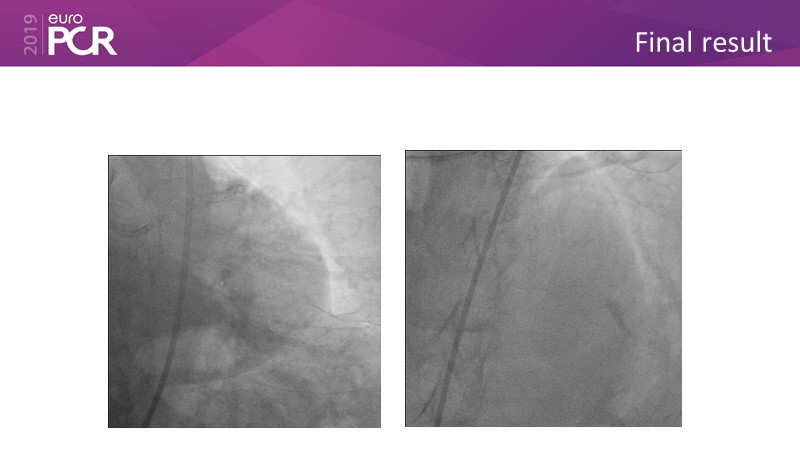

Distal left main stenosis: how to treat optimally with dedicated bifurcation stent BiOSS Lim C. Case-based session